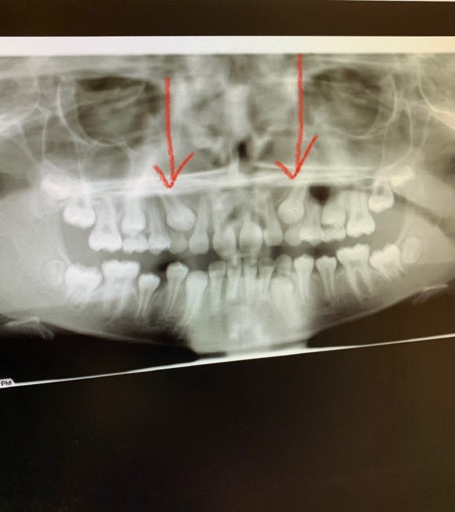

Hi, I have a frenulum on the right side of my mouth. It connects to my gums about 1cm behind the upper and lower back molars. It has become tight and painful. Have you ever seen anything like this? Is it safe to have it cut? I will attempt to add a photo. Thank you, H. Jay Graber

Impacted Canines

What is the procedure for impacted Canines that are at the top only for both canines and they are in the top of the gums on the outside (not in palette). I have an X-ray. ITS FOR MY DAUGHTER... 12 years old and 2 months.